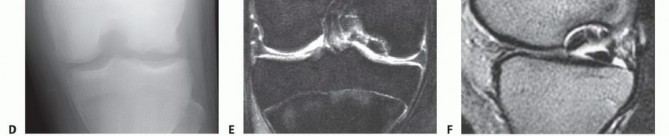

Avascular Necrosis

In AVN, plain films evaluate for evidence of collapse and secondary arthrosis (

FIG 9

). Once present, core decompression is not indicated.

MRI aids in determining the location and extent of subchondral bone involvement. Only lesions extending to subchondral bone are at risk for collapse and, therefore, appropriate for core decompression.

AVN most commonly is seen in the hip. The knee is the second most common location but accounts for only about 10% as many cases as the hip. AVN can affect the femur, tibia, or both; is bilateral in over 80% of cases; and usually involves multiple condyles (

FIG 3A

).

AVN involves a larger area of subchondral bone, with extension into the epiphysis and even the metaphysis or diaphysis.

Spontaneous Osteonecrosis of the Knee

Spontaneous osteonecrosis of the knee is different from AVN. Spontaneous osteonecrosis of the knee occurs in patients older than 55 years, involves only one condyle (most commonly medial), and is unilateral in 99% of cases (

FIG 3B,C

The pathologic lesion in spontaneous osteonecrosis of the knee is a stress fracture of subchondral bone with collapse of the articular surface and secondary joint incongruity and pain.

FIG 3 • A. MRI scan of AVN involving multiple condyles with extension into the metaphysis. B,C. MRI scans of spontaneous osteonecrosis of the knee involving the medial condyle only. Note the edema adjacent to the involved area.